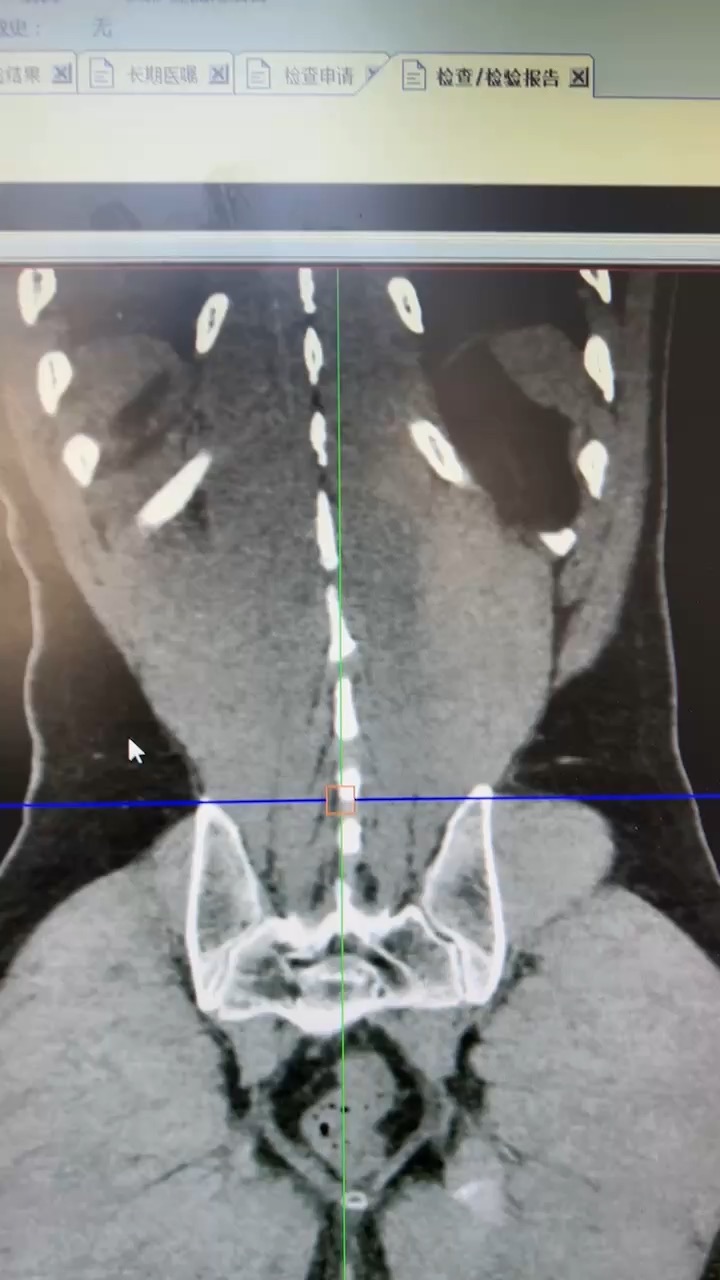

鹿角形结石你见过吗?这样的结石如何治疗?

现病史:患者2周前无明显诱因出现左侧腰腹部疼痛,行泌尿系超声示:1.双肾囊肿;2.左肾结石(多发);3前列腺增生伴钙化。今为进一步诊治,来我院,门诊以“左侧肾结石、前列腺增生、双侧单纯性肾囊肿”患者精神饮食睡眠尚可,大便正常。尿常规:白细胞(3+),硝酸盐(+),尿培养大肠埃希菌,耐药。